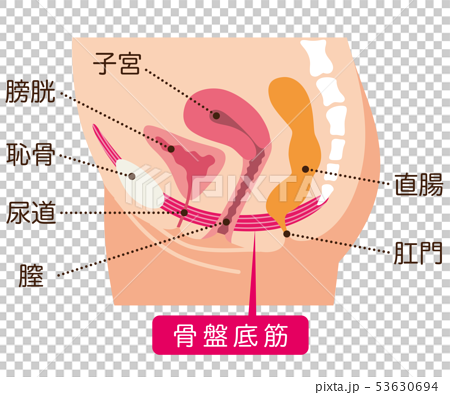

Pelvic Floor Muscles Stock Illustration

骨盤臓器脱 亀田メディカルセンター ウロギネ 女性排尿機能センター

女性骨盤 内臓 骨盤底筋付 6分解モデル 日本スリービー サイエンティフィック

女性骨盤 内臓 骨盤底筋付 6分解モデル 日本スリービー サイエンティフィック